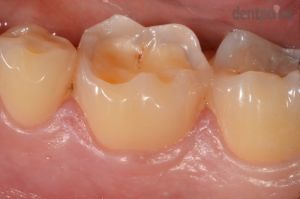

Esztétikus fogtömés készítése

Savas refluxtól szenvedő páciensünk őrlőfoga sajnos erőteljes kopásnak indult, azonban kompozit tömőanyaggal sikerült tökéletesen helyreállítani a sérült fogat!

1) Rágófelszín kopása

2) Esztétikus fogtömés